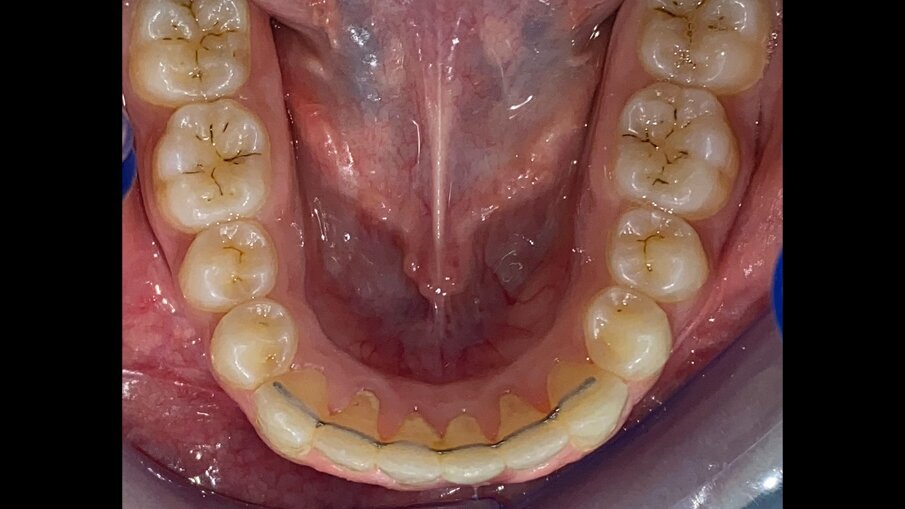

All’esame obiettivo intraorale si riscontra sul piano frontale un severo morso profondo con precontatto traumatico degli incisivi superiori contro la papilla retroincisiva e le rughe palatine anteriori durante la massima intercuspidazione, con overbite di 10 mm (Fig. 5). Dalle foto laterali si evidenzia una malocclusione di Classe II divisione 2 con scissor bite dell’elemento 1.5 (Figg. 6, 7), mentre dalle foto occlusali si rileva un grave affollamento con contrazione di entrambe le arcate maggiore nella zona premolare (Figg. 8, 9). L’analisi di Bolton mostra un eccesso superiore 3-3 di 2,34 mm (73,6%) e 6-6 di 2,76 mm (88,8%). L’analisi cefalometrica evidenzia una Classe II scheletrica, modello facciale normodivergente, angolo interincisale aumentato, incisivi superiori e inferiori retroinclinati (Fig. 10). La radiografia panoramica mostra la presenza dei germi dei terzi molari, assenza di parallelismo tra le radici dei premolari inferiori (Fig. 11) e una sovraeruzione degli incisivi inferiori che crea un doppio piano tra gli incisivi e i molari, segno di una curva di Spee molto profonda.

Fig. 9_Occlusale inferiore pre-trattamento.